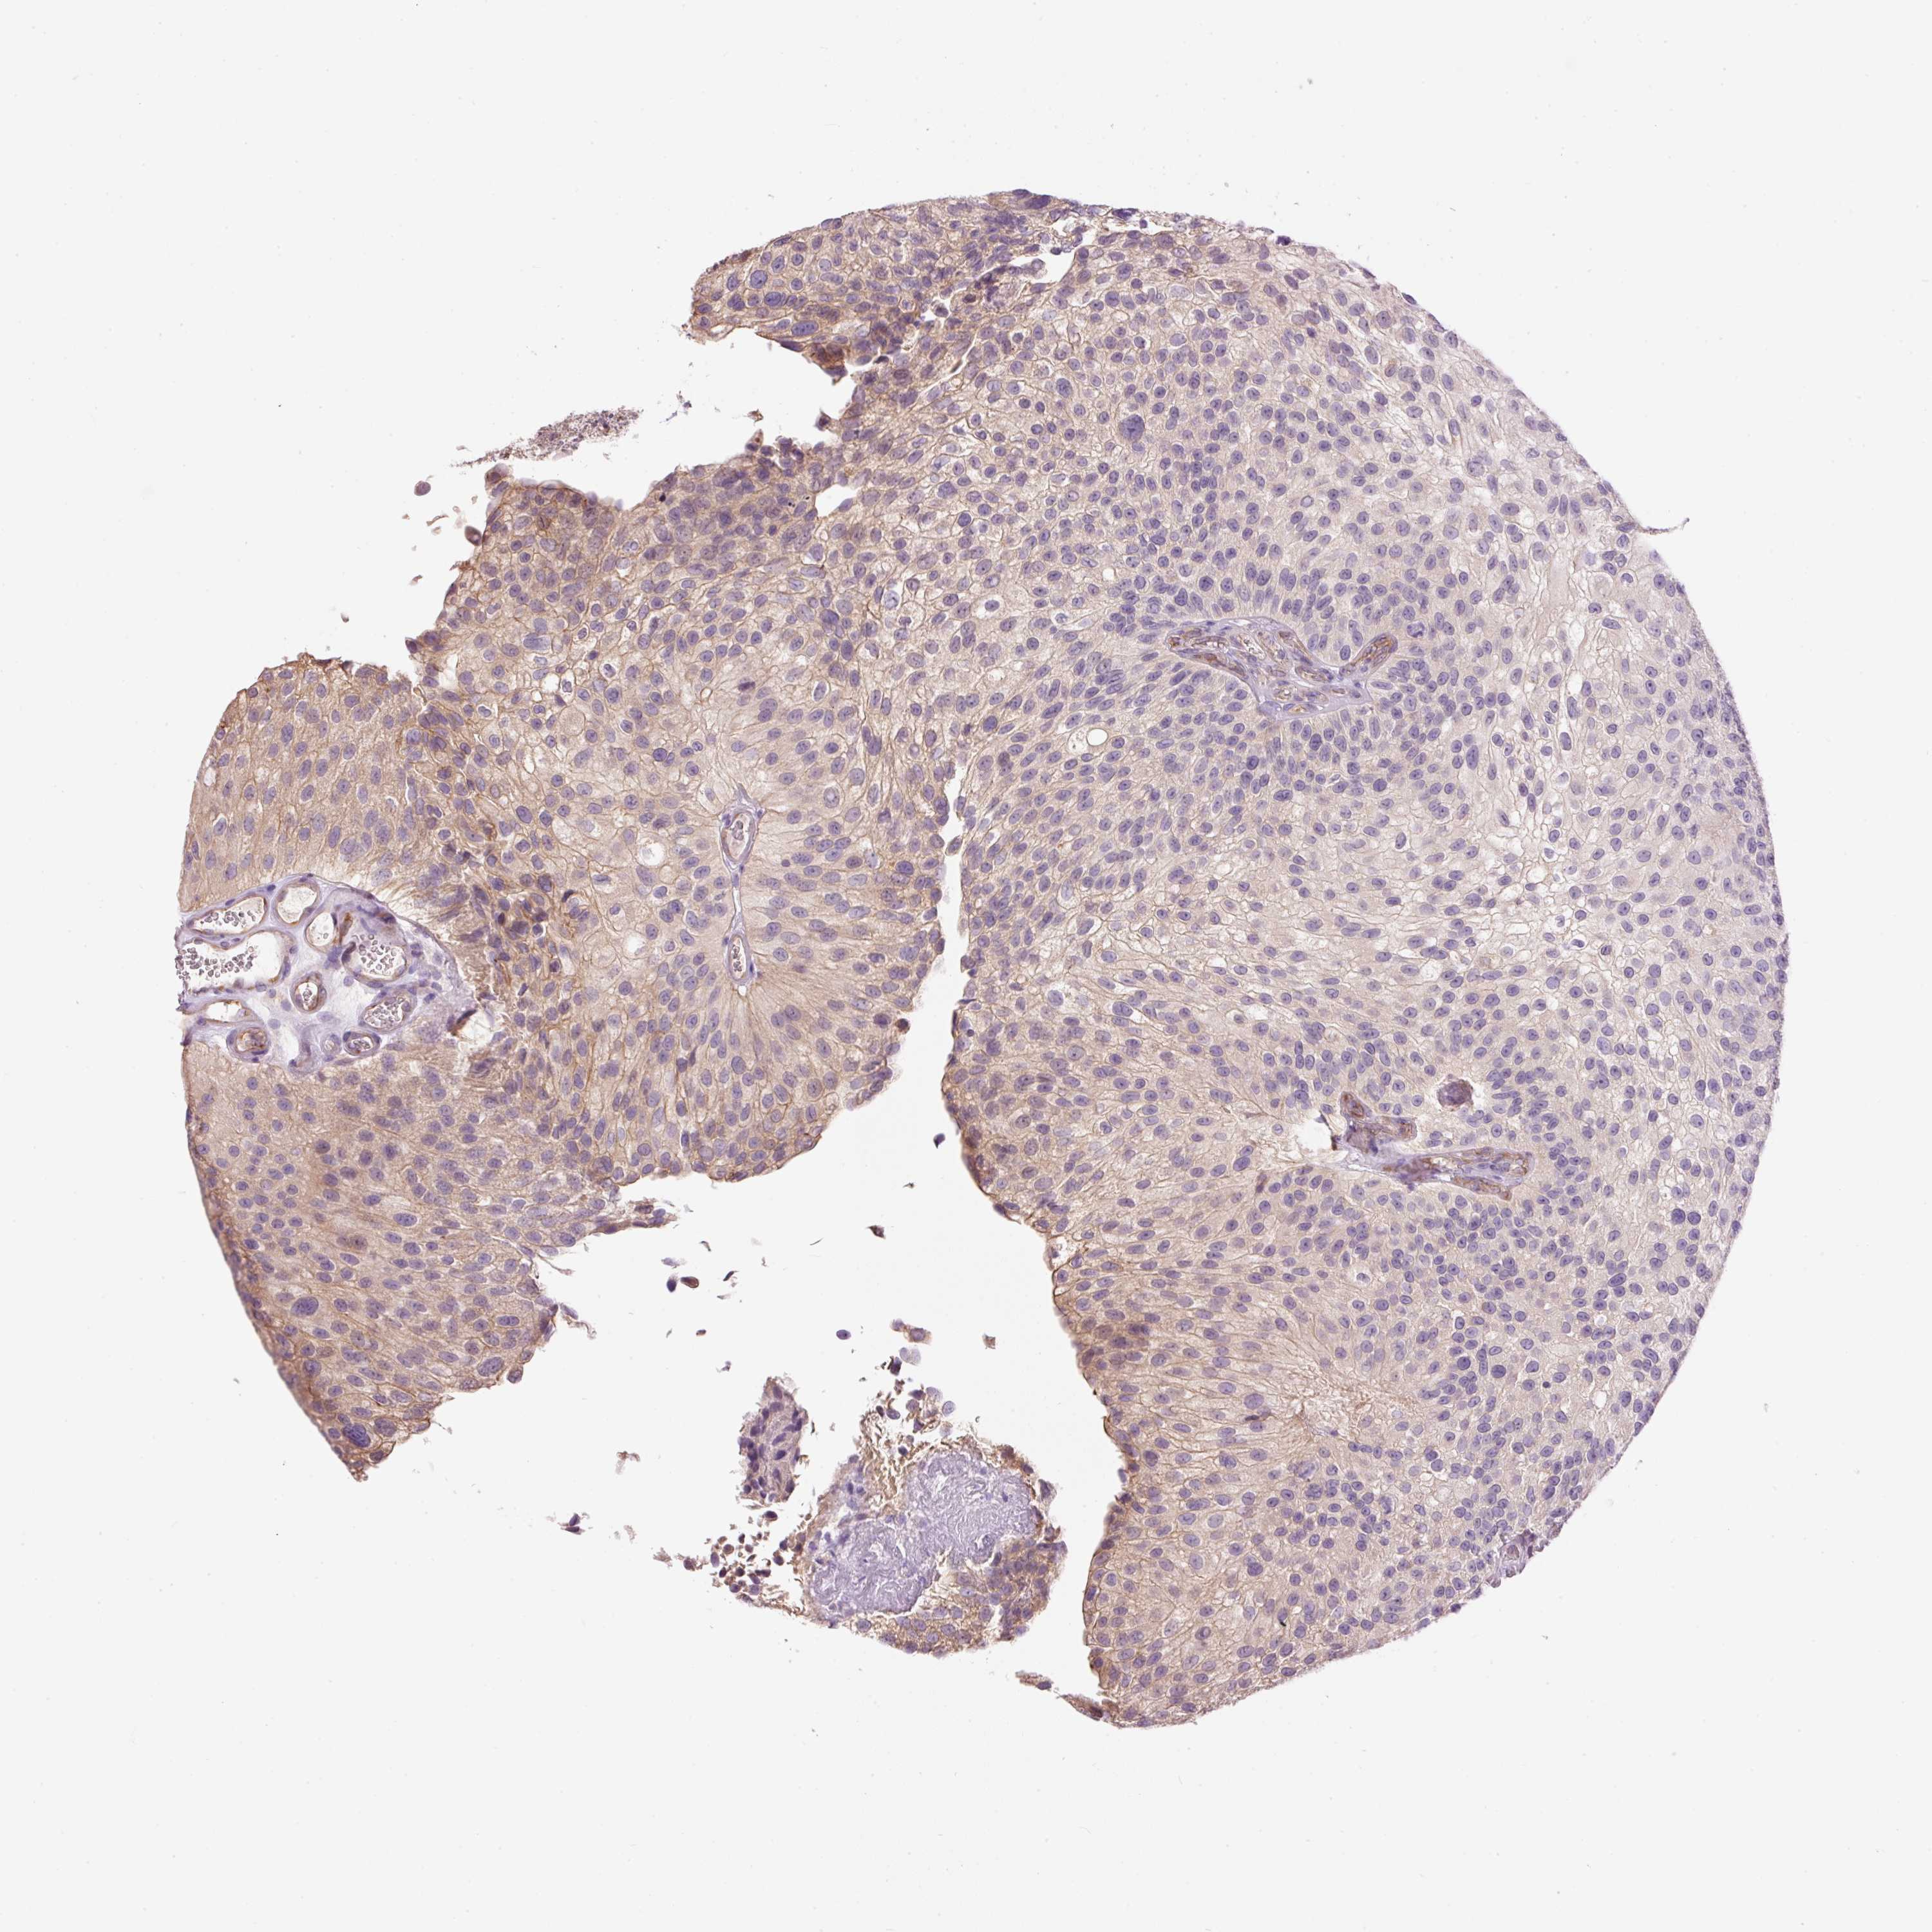

UROTHELIAL CANCER - Protein expressioni

A mouse-over function shows sample information and annotation data. Click on an image to view it in a full screen mode. Samples can be filtered based on level of antibody staining by selecting one or several of the following categories: high, medium, low and not detected. The assay and annotation is described here.

Note that samples used for immunohistochemistry by the Human Protein Atlas do not correspond to samples in the TCGA dataset.

Antibody stainingi

Antibody staining in the annotated cell types in the current human tissue is reported as not detected, low, medium, or high, based on conventional immunohistochemistry profiling in selected tissues. This score is based on the combination of the staining intensity and fraction of stained cells.

Each image is clickable and will lead to virtual microscopy that enables deeper exploration of all samples and also displays staining intensity scores, fraction scores and subcellular localization as well as patient and tissue information for each sample.

Antibody HPA050409

Antibody HPA054211

Urothelial carcinoma, Low grade

Urothelial carcinoma, High grade

Urothelial carcinoma, NOS